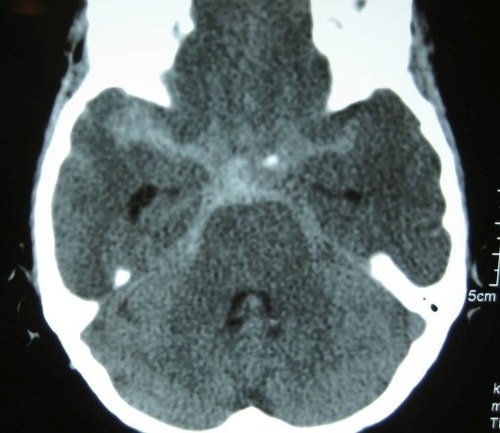

下記図表1のCT画像のように、検査をすれば診断は一瞬にして可能なのです。